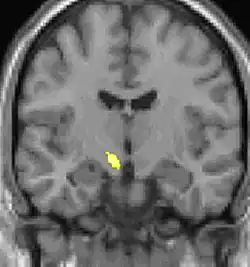

![]() |

| Tomografia PET mostrando áreas ativadas na dor. | ||

| VBM mostrando diferenças estruturais entre cérebros | ||